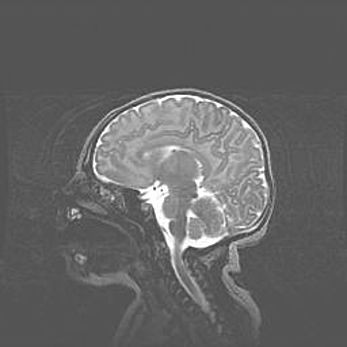

Аномалия Денди-Уокера. Признаки гипоплазии мозолистого тела.

Возраст: 5 месяцев 3 дня

Вес: 5550 г

Пол: мужской

Окружность головы: 39 см

Срок гестации: 40 недель

Аномалия Денди-Уокера – это порок развития головного мозга, для которого характерна триада симптомов: гипотрофия или аплазия червя мозжечка и/или полушарий мозжечка, расширение четвёртого желудочка с формированием ликворной кисты задней черепной ямки, гипертензионная гидроцефалия различной степени.

Гипоплазия мозолистого тела относится к дефектам внутриутробного этапа развития мозговой ткани, возникающим в процессе закладки структур головного мозга, что происходит на начальных этапах развития эмбриона.